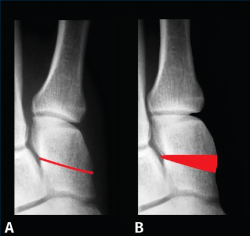

Figura 13. Caso del Dr. Martín Ferreyra. Imágenes radiológicas preoperatorias. A: dorsoplantar; B: perfil; C: axial de los sesamoideos.

Figura 14. Caso del Dr. Martín Ferreyra. Imágenes radiológicas postoperatorias. A: dorsoplantar; B: perfil; C: axial de los sesamoideos. Obsérvese la corrección obtenida y la ubicación de los sesamoideos antes y después de la cirugía.

Es por ello que en la actualidad autores como E. y P. Wagner(68) realizan una osteotomía tridimensional, no solo en el plano transversal, a la que denominan PROMO. En el caso de la artrodesis cuneometatarsiana sucede lo mismo y una de las tendencias actuales es realizar un Lapidus modificado tridimensional(69,70), como puede verse en el caso de M. Ferreyra (Figuras 13 a 15), en el que la estabilización con 2 placas permite una carga precoz.